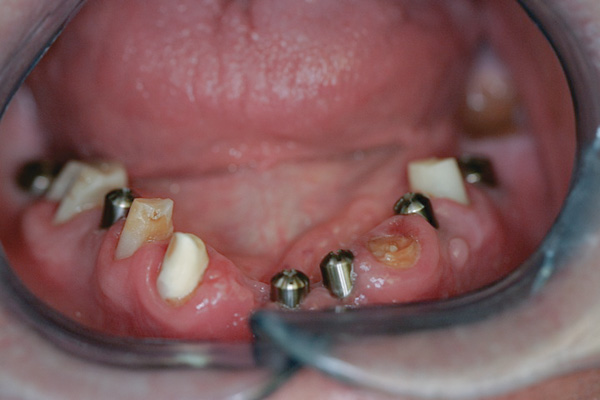

Background: In this case, the patient had a failing mandibular and maxillary dentition due to caries secondary to radiation-induced xerostomia. The patient had had a radical neck dissection to remove a squamous cell carcinoma of the throat 9 years prior to his prosthodontic consultation with the authors. The patient reported a history of radiation therapy following surgery, but did not have a shielding stent. A staged approach was used so as to avoid removable prosthetics on his severely dry soft tissues. He chose to treat his mandibular issues first. Figure 9 shows healing abutments next to the temporarily retained natural teeth, and Figure 10 shows the first-stage custom abutments inserted with relatively good gingival contour and no recession. Recession was clearly seen around all first-stage abutments following adjacent extractions and second-stage implant placement (Figure 11).

Results: The decision was made to remove these abutments and make a fixture-level impression of all the implants so that both new and first-stage abutments could be milled together for parallelism and proper gingival margin location. Because this requires the removal of the first-stage abutments that were retaining the provisional prosthesis, temporary abutments were placed prior to removal of all custom abutments in order to assure proper seating and vertical dimension of the provisional. These temporary abutments then retained the provisional while all custom abutments were fabricated and/or milled in the laboratory. Figure 12 shows the placement of the remilled (first-stage implants) and new (second-stage implants) custom abutments.

Figure 9 Healing abutments.

Figure 9

Figure 10 First-stage custom abutments.

Figure 10

Figure 11 Recession evident around first-stage abutments following adjacent extractions and second-stage implant placement.

Figure 11

Figure 12 Remilled and new custom abutments.

Figure 12